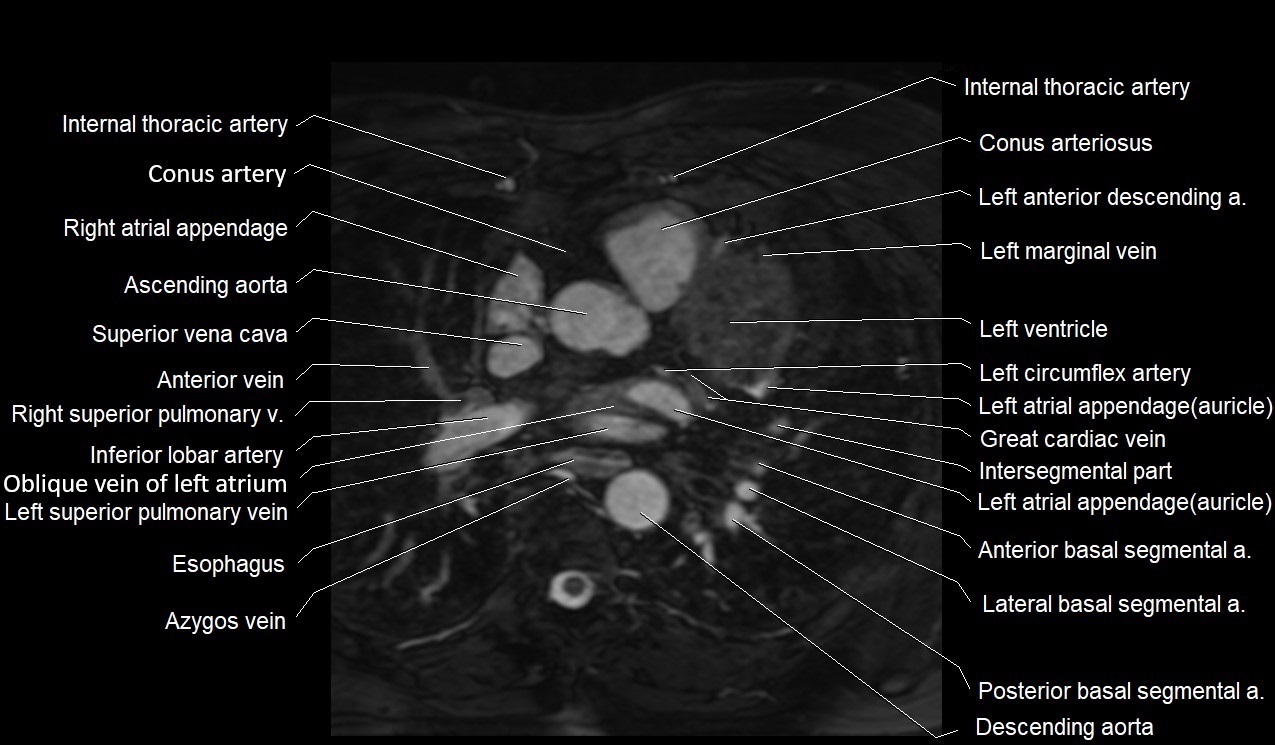

CT images